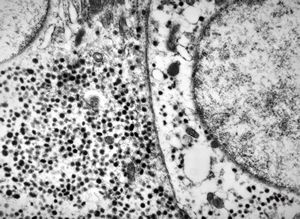

F, 71y. | carcinoid … metastasis to lymphonode